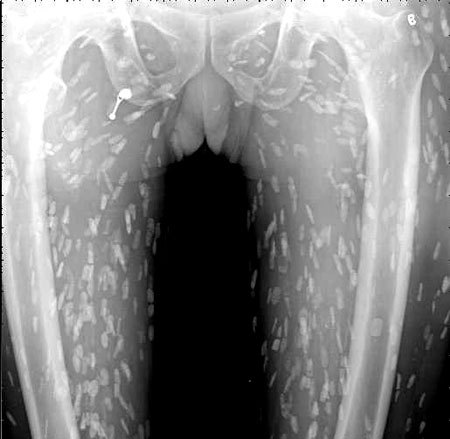

광둥성 푸산시 순더 지역에서 한 남성은 회를 섭취한 뒤, 복부 통증과 피부 가려움증 증상을 겪었습니다. 이로 인해 그는 난팡 의과대학 부속병원을 찾아 진료를 받았습니다. 의사는 이 환자의 증상을 확인하기 위해 엑스레이를 촬영하였고, 이 사진에서는 그의 온몸에 기생충이 퍼져 있는 것을 확인할 수 있었습니다. 이러한 기생충은 촌충 또는 열두 조충이라고 불리는 벌레로서, 사람의 장내에서 기생하는 것으로 알려져 있습니다.